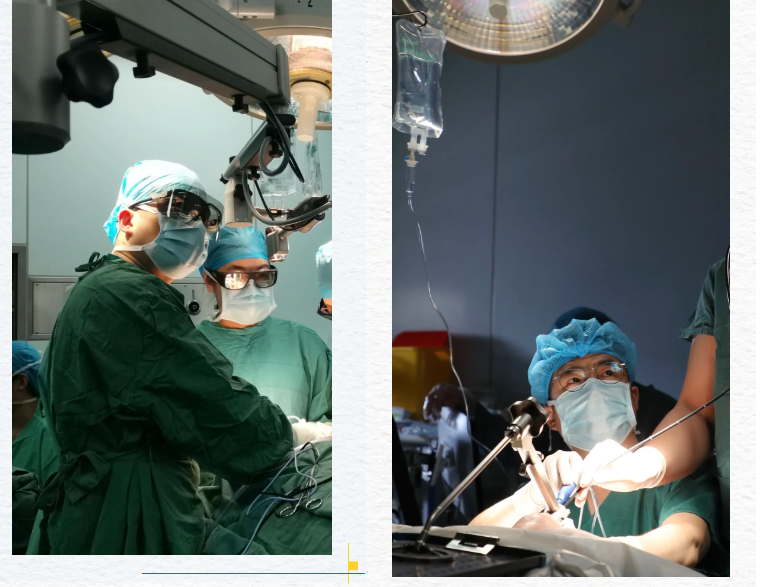

今天,完成了一台有些特别的手术。

没有开阔的视野,所有操作都在口腔这个“深井”里进行,凭借内镜的方寸之光。器械的每一次前进,都紧贴着重要的血管与神经,如履薄冰。肿物巨大,与周围组织粘连紧密,剥离的每一步,都像是在拆除一个精密而危险的电路。

两个小时。

一百二十分钟的屏息凝神。内镜下的世界被放大,时间如同静止,吸引器的嘶鸣是唯一的背景音。我们像微雕工匠,在生命的险峰上谨慎地雕琢。终于,那个完整的、灰白色的瘤体,被逐步的分离、取出。

这条路很难,视野受限,操作局促,容错率极低。但今天,我们和患者一起,证明了它的价值。